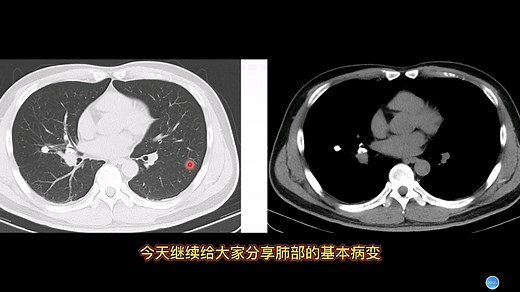

Lung Calcification 的热门建议 |

- Granuloma Lung

Causes - Lung

Nodule Size Chart - Calcification

Treatments - Nodules On Lungs

in CT Scan - Calcified

Lungs - Calcification